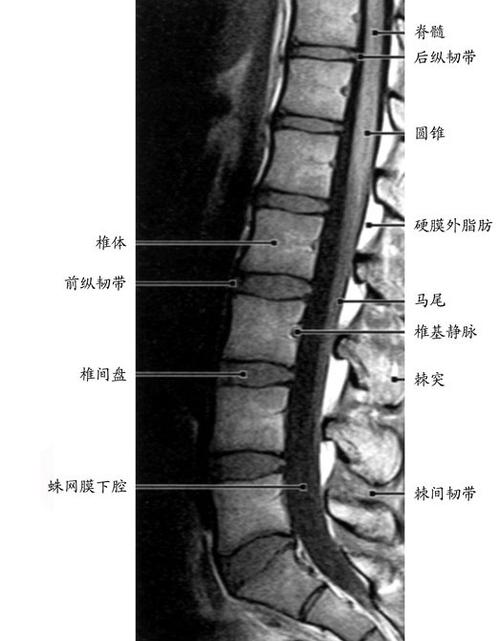

腰椎穿刺解剖结构图解

腰椎穿刺解剖结构图解,腰麻层次解剖图

腰椎:椎体较大;棘突板状水平伸向后方,相邻棘突间间隙宽,可作腰椎穿刺